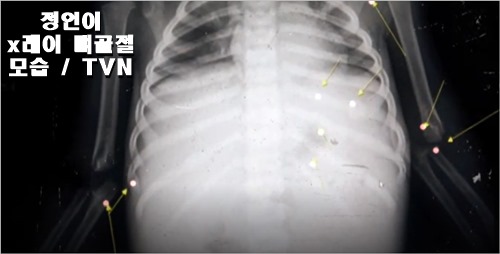

아이들의 뼈는 잘 안뿌러지는데 이정도면 무슨 일이 있었을까? 췌장 절단 및 7군데 뼈 골절로 인한 외력에 의한 사망으로 최종 국가수 의견이 나온 상태인데요 .. 이미 일어나버린 일을 어떻게 되돌릴 수 있나 ..와...글만 아니면 저도 그 분의 얼굴한번 보러 가고 싶기는 합니다.

현재 정인이는 사망한 상태이고 입양 271일만에 사망한 상태라고 합니다. 주차장에서의 CCTV에도 학대의 모습들이 기사로 나오면서 입양전 정인이의 생전 모습이 동영상으로 보고 있습니다. 더 안타까운 것은 3번째 신고는 소아과 전문의사가 해서 아이와 양부모가 분리가 되어야 된다고 강력하게 제기된 부분의 기사를 접하고 TVN화면을 보면서 눈물을 적시면서 안타까운 죽음을 보게 되었습니다.